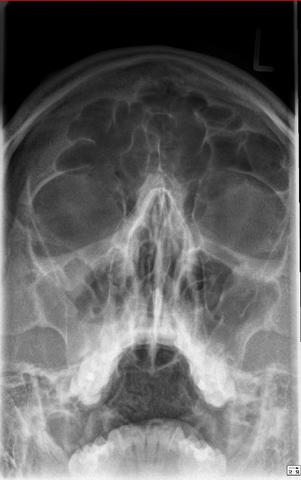

Wie lange dauert eine sinusitis. Von einer Nasennebenhöhlenentzündung können verschiedene Hohlräume in den Gesichtsknochen betroffen. Wie lange dauert das. Eine Nasennebenhöhlenentzündung Sinusitis kann je nach Form mehrere Wochen dauern.

Die Dauer einer akuten Nasennebenhöhlenentzündung beträgt bei entsprechender Behandlung normalerweise 8. Allerdings kann eine Sinusitis nicht nur akut auftreten sondern auch chronisch verlaufen. Dauert die Sinusitis länger als 12 Wochen an handelt es sich um eine chronische Sinusitis.

Hat sich eine Sinusitis auf die Orbita ausgedehnt kann ein Abszeß in wenigen Stunden zur Erblindung führen. Was ist eine chronische Sinusitis. Wird eine akute Sinusitis nicht auskuriert kann dies auch zu ernsten Folgen führen.

Wie lange dauert es die jeweils in 90 Tage anhaltend eingestuft werden. Sobald die Nebenhöhlenentzündung länger als 12 Wochen andauert bezeichnet man sie als chronisch was sie gleichzeitig schwieriger zu behandeln macht.